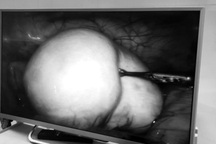

Dịch đặc quánh được hút ra từ ổ bụng và khối u buồng trứng.

Trải qua nhiều giờ phẫu thuật, các bác sĩ đã lấy ra hơn 15 lít dịch đặc quánh, phát hiện u buồng trứng 2 bên bị vỡ vỏ, nhiều khối di căn kích thước 5 - 7 cm. Khối u xâm lấn thành đại tràng sigma, di căn mạc nối lớn, dính mạch chậu trái nên sau khi cắt u buồng trứng 2 bên, cắt đoạn đại tràng sigma, các bác sĩ đã thực hiện làm hậu môn nhân tạo cho bệnh nhân.